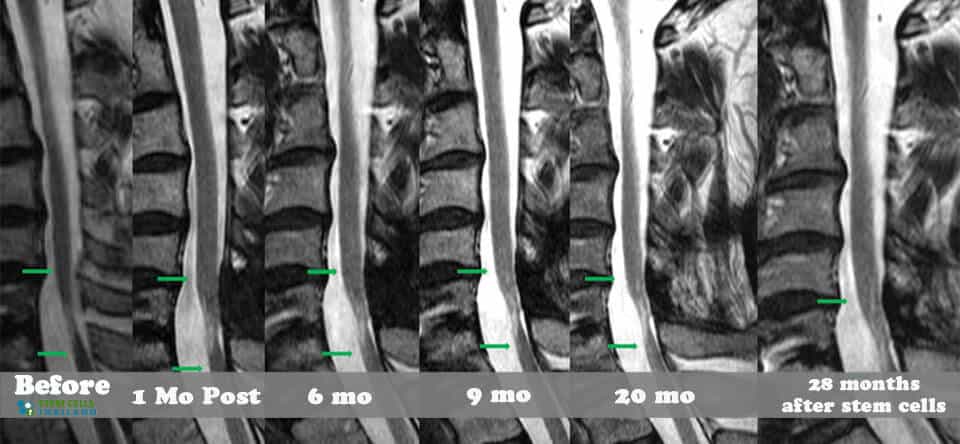

脊髓損傷的細(xì)胞療法側(cè)重于大腦和身體之間軸突的再生,這些軸突在事故發(fā)生后受到嚴(yán)重限制或不存在。我們針對脊髓損傷的干細(xì)胞移植可以幫助患者消除疼痛,恢復(fù)膀胱和腸道功能,恢復(fù)失去的感覺,并再生內(nèi)臟運動神經(jīng)元,同時最大限度地減少其他問題,例如損傷引起的痙攣或抑郁。傳統(tǒng)治療不解決再生問題,而是側(cè)重于疼痛管理、康復(fù)和減少繼發(fā)性損傷。

基于細(xì)胞的治療采取更積極主動的方法,通過刺激/增強受損細(xì)胞和組織的修復(fù)來促進(jìn)人類的自然修復(fù)周期。修復(fù)受傷的脊髓和竹脊柱需要超越任何傳統(tǒng)技術(shù)來幫助您恢復(fù)部分/全部失去的功能。臨床試驗表明,細(xì)胞更新和死亡是非常正常的,當(dāng)身體細(xì)胞受傷或老化時,細(xì)胞會自然發(fā)生。這些死亡細(xì)胞通常被健康和受損的細(xì)胞包圍。我們針對坐骨神經(jīng)痛和椎管狹窄的治療方案通過利用神經(jīng)生長因子和旁分泌信號傳導(dǎo)的靶向細(xì)胞因子療法,有助于促進(jìn)這些死亡或受傷細(xì)胞的愈合欺騙身體重新開始愈合過程。

我們脊柱損傷治療中心的目標(biāo)是幫助以自然和安全的方式修復(fù)損傷。我們的治療是在細(xì)胞水平上進(jìn)行的,僅影響靠近影響點的區(qū)域。如果受傷時間不到兩年,積極的結(jié)果可能會非常顯著。對于那些患有老年損傷、創(chuàng)傷性腦損傷、嚴(yán)重椎間盤退變、股骨頭壞死、周圍神經(jīng)病變或脊髓性肌肉萎縮的人來說,隨著時間的推移,完全康復(fù)的機會變得更加困難。

組織、軟骨或韌帶的新?lián)p傷對干細(xì)胞治療的反應(yīng)要好得多。治療后的康復(fù)需要大量的奉獻(xiàn)和康復(fù)訓(xùn)練。初次治療后約2-3個月,身體改善明顯,且效果是永久性的。[2]